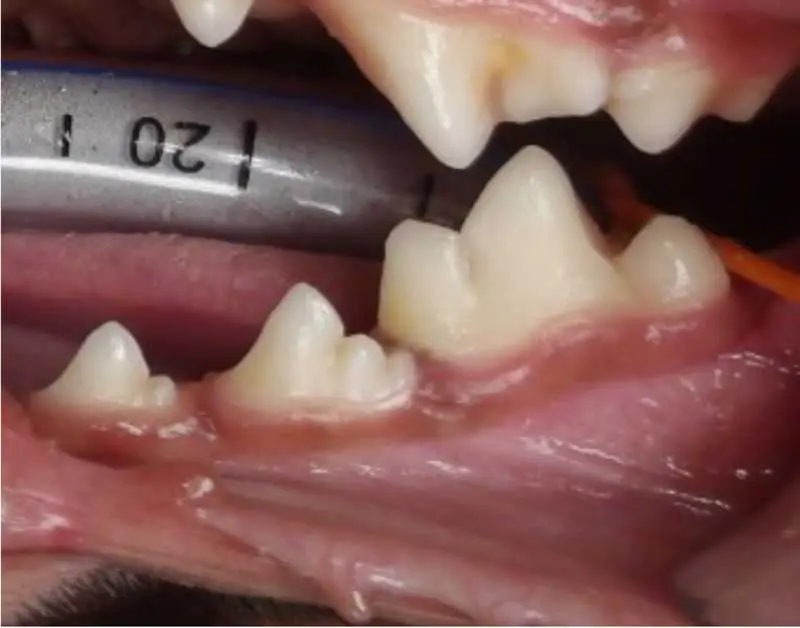

Periodontal probe

- Measures periodontal pocket depth. The probe (Figure 7) is gently inserted along the gingival margin around each tooth to measure the depth of the sulcus (the space between the tooth and gingiva). The sulcus depth is typically 1mm to 3mm in a healthy medium to large breed dog. In small or toy breeds, it is slightly shallower at 1mm to 2mm. Depths greater than this may indicate periodontal pocketing or loss of attachment or foreign body.

- Measures ulceration/oral mass size.

- Identifies gingival inflammation. By probing the sulcus around each tooth, the operator can assess whether the gingiva is inflamed, swollen or bleeding.

- Assesses tooth mobility. The probe can also be used to check for signs of tooth mobility, which can indicate advanced periodontal disease, in which the tooth is no longer firmly anchored to the bone (Table 1).